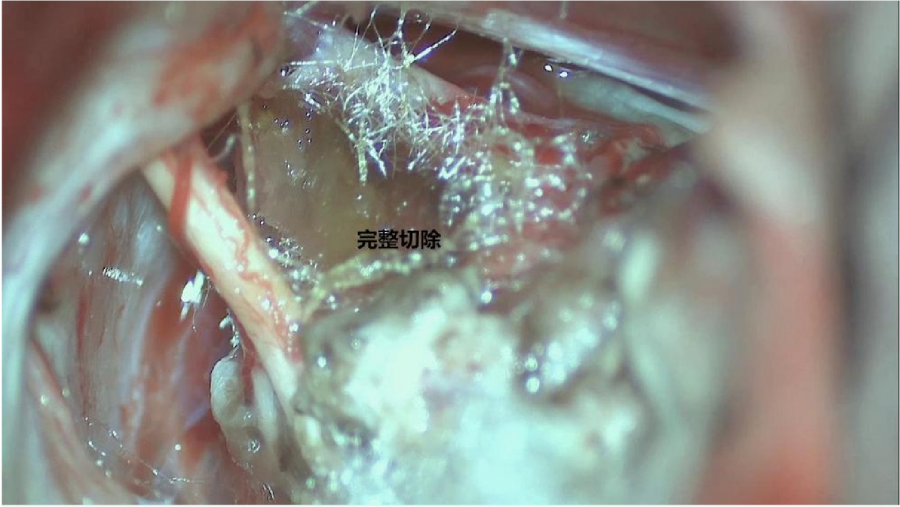

⾏左侧远外侧⼊路脑⼲⾎管畸形切除术,术中所⻅:

术后患者轻度⾯瘫House-Brackmann分级III级,可恢复。

术后CTA显⽰:畸形⾎管团消失

患者康复出院,半年后复查,如有⼩量的畸形⾎管团可以考虑伽⻢⼑治疗。